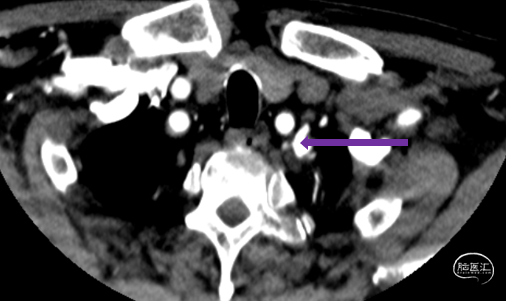

患者出现意识模糊、呕吐、胸闷等不适,查体:血压升高(血压200/100mmHg),神清,对答切题,伸舌居中,查体部分配合,四肢肌力5级,双眼向右凝视伴水平眼震。

立即行Dyna-CT,未见脑出血表现,立即予以尼卡地平及尼莫地平降压,动脉静推负荷量替罗非班。

造影见LV闭塞,立即沿0.014*200cm 通桥北斗SS™神经血管导丝置入3mm*16mm 药物球扩支架至LV1。

压力泵逐渐加压球扩支架到8atm, 支架打开良好,造影示残余狭窄0%。

双侧锁骨下动脉造影见椎动脉、基底动脉血流通畅,远端未见栓塞表现。